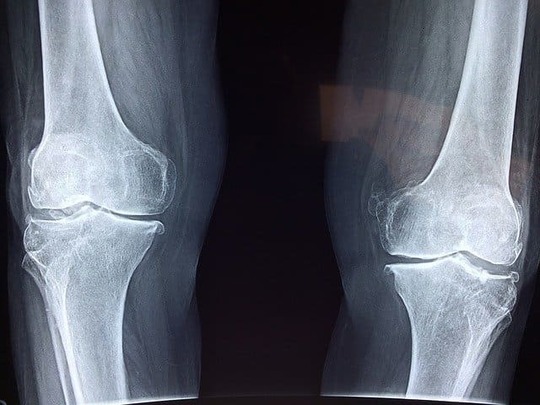

捻挫の主な症状は、腫れ、熱感、痛み

捻挫の主な症状は、腫れ、熱感、痛みです。靭帯に傷がつくため、関節の周りの血管が切れてしまいます。そのため、内出血が起きて腫れが現れるのです。腫れによって炎症が起き、痛みを感じます。

捻挫の症状の程度は3つに分けることができます。

靭帯の断裂が一部分に起き、痛みと軽い腫れが現れる第1度、靭帯が部分的に断裂し、痛みと腫れとともに関節の運動の制限が起きる第2度、靭帯が完全に断裂し、関節が不安定になり、晴れ、痛み、熱感が強く現れる第3度です。